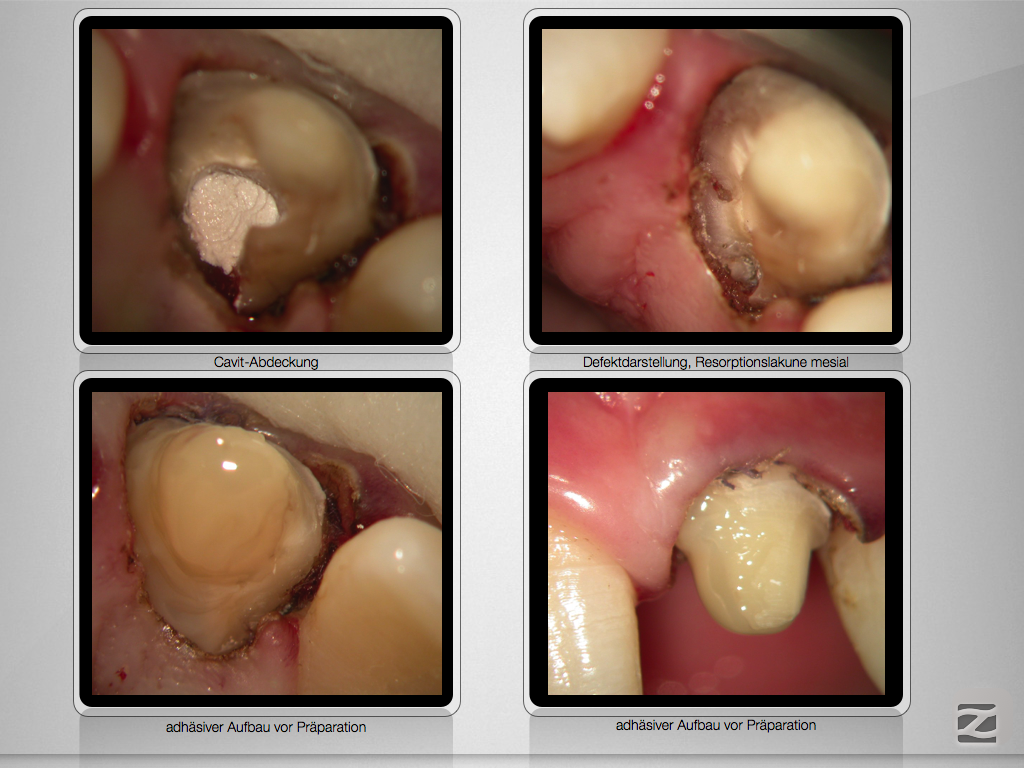

Komplizierte Kronen-Wurzelfraktur